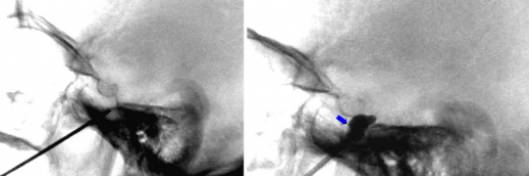

图11. 调整C形臂以提供隧道视角,X线方向与穿刺针平行。该图从斜角方向暴露了骨孔,保证准确地定位穿刺针和骨孔。经常地,可以通过对透视光束进行微调暴露骨孔的”正面”。这种方法有助于识别外侧下颌骨升支和内侧上颌骨之间的骨孔。

图12. X线斜位图示针尖恰好位于骨孔后方(左图,白箭头);微调后确认穿刺针在骨孔内(右图)。

当穿入卵圆孔时,经常出现三叉神经抑制反应和咬肌、翼状肌收缩。在较难穿刺的骨孔,这种收缩反应可以引导穿刺针沿着颅底安全的区域寻找骨孔。一旦穿刺针进入骨孔,应该将它再穿入最多0.5cm的距离,直到侧面X线确认其位置。